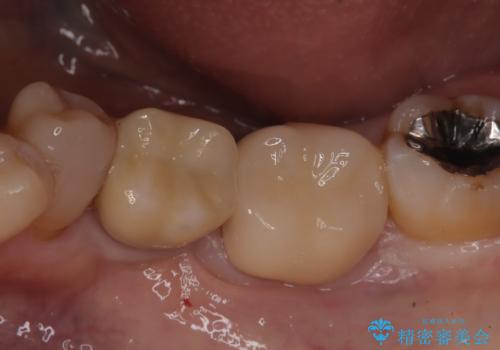

メタルインレーの下は。クラックラインを認めた歯。

- 定期検診にて、奥歯にクラックラインを認めました。

放置すると、抜歯になる可能性も高いため早めの治療を提案し、クラウンにて修復治療を行なっております。

術前説明にてクラックラインを認めることや治療の選択肢及び予後について理解していただいた上で、保存を希望されております。歯髄症状が出なかったため抜髄はせずに治療を完了しております。